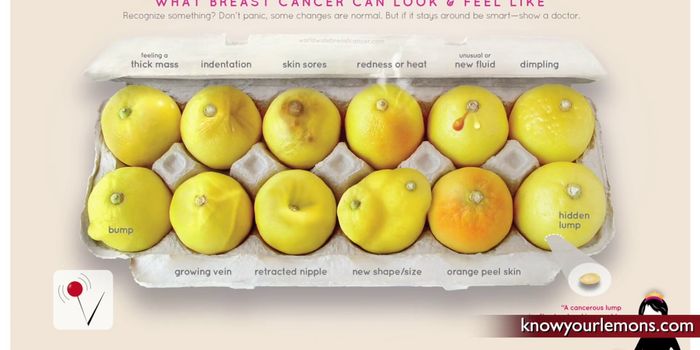

OCT 18, 2017VideosIn 2016, an estimated 246,660 women in the US was diagnosed with breast cancer - a disease that currently ranks as one o ...

OCT 06, 2017VideosOctober is Breast Cancer Awareness Month; however, a recent study shows that many women are not aware of the issue of ov ...